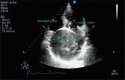

Coronary artery fistulas are rare coronary-cardiac anomalies, which occasionally become symptomatic. We herein report a case of a 54-year-old woman with a huge conus branch aneurysm resulting from an abnormal fistula between the conus branch and the upper portion of the right atrium, which was successfully removed by surgery.